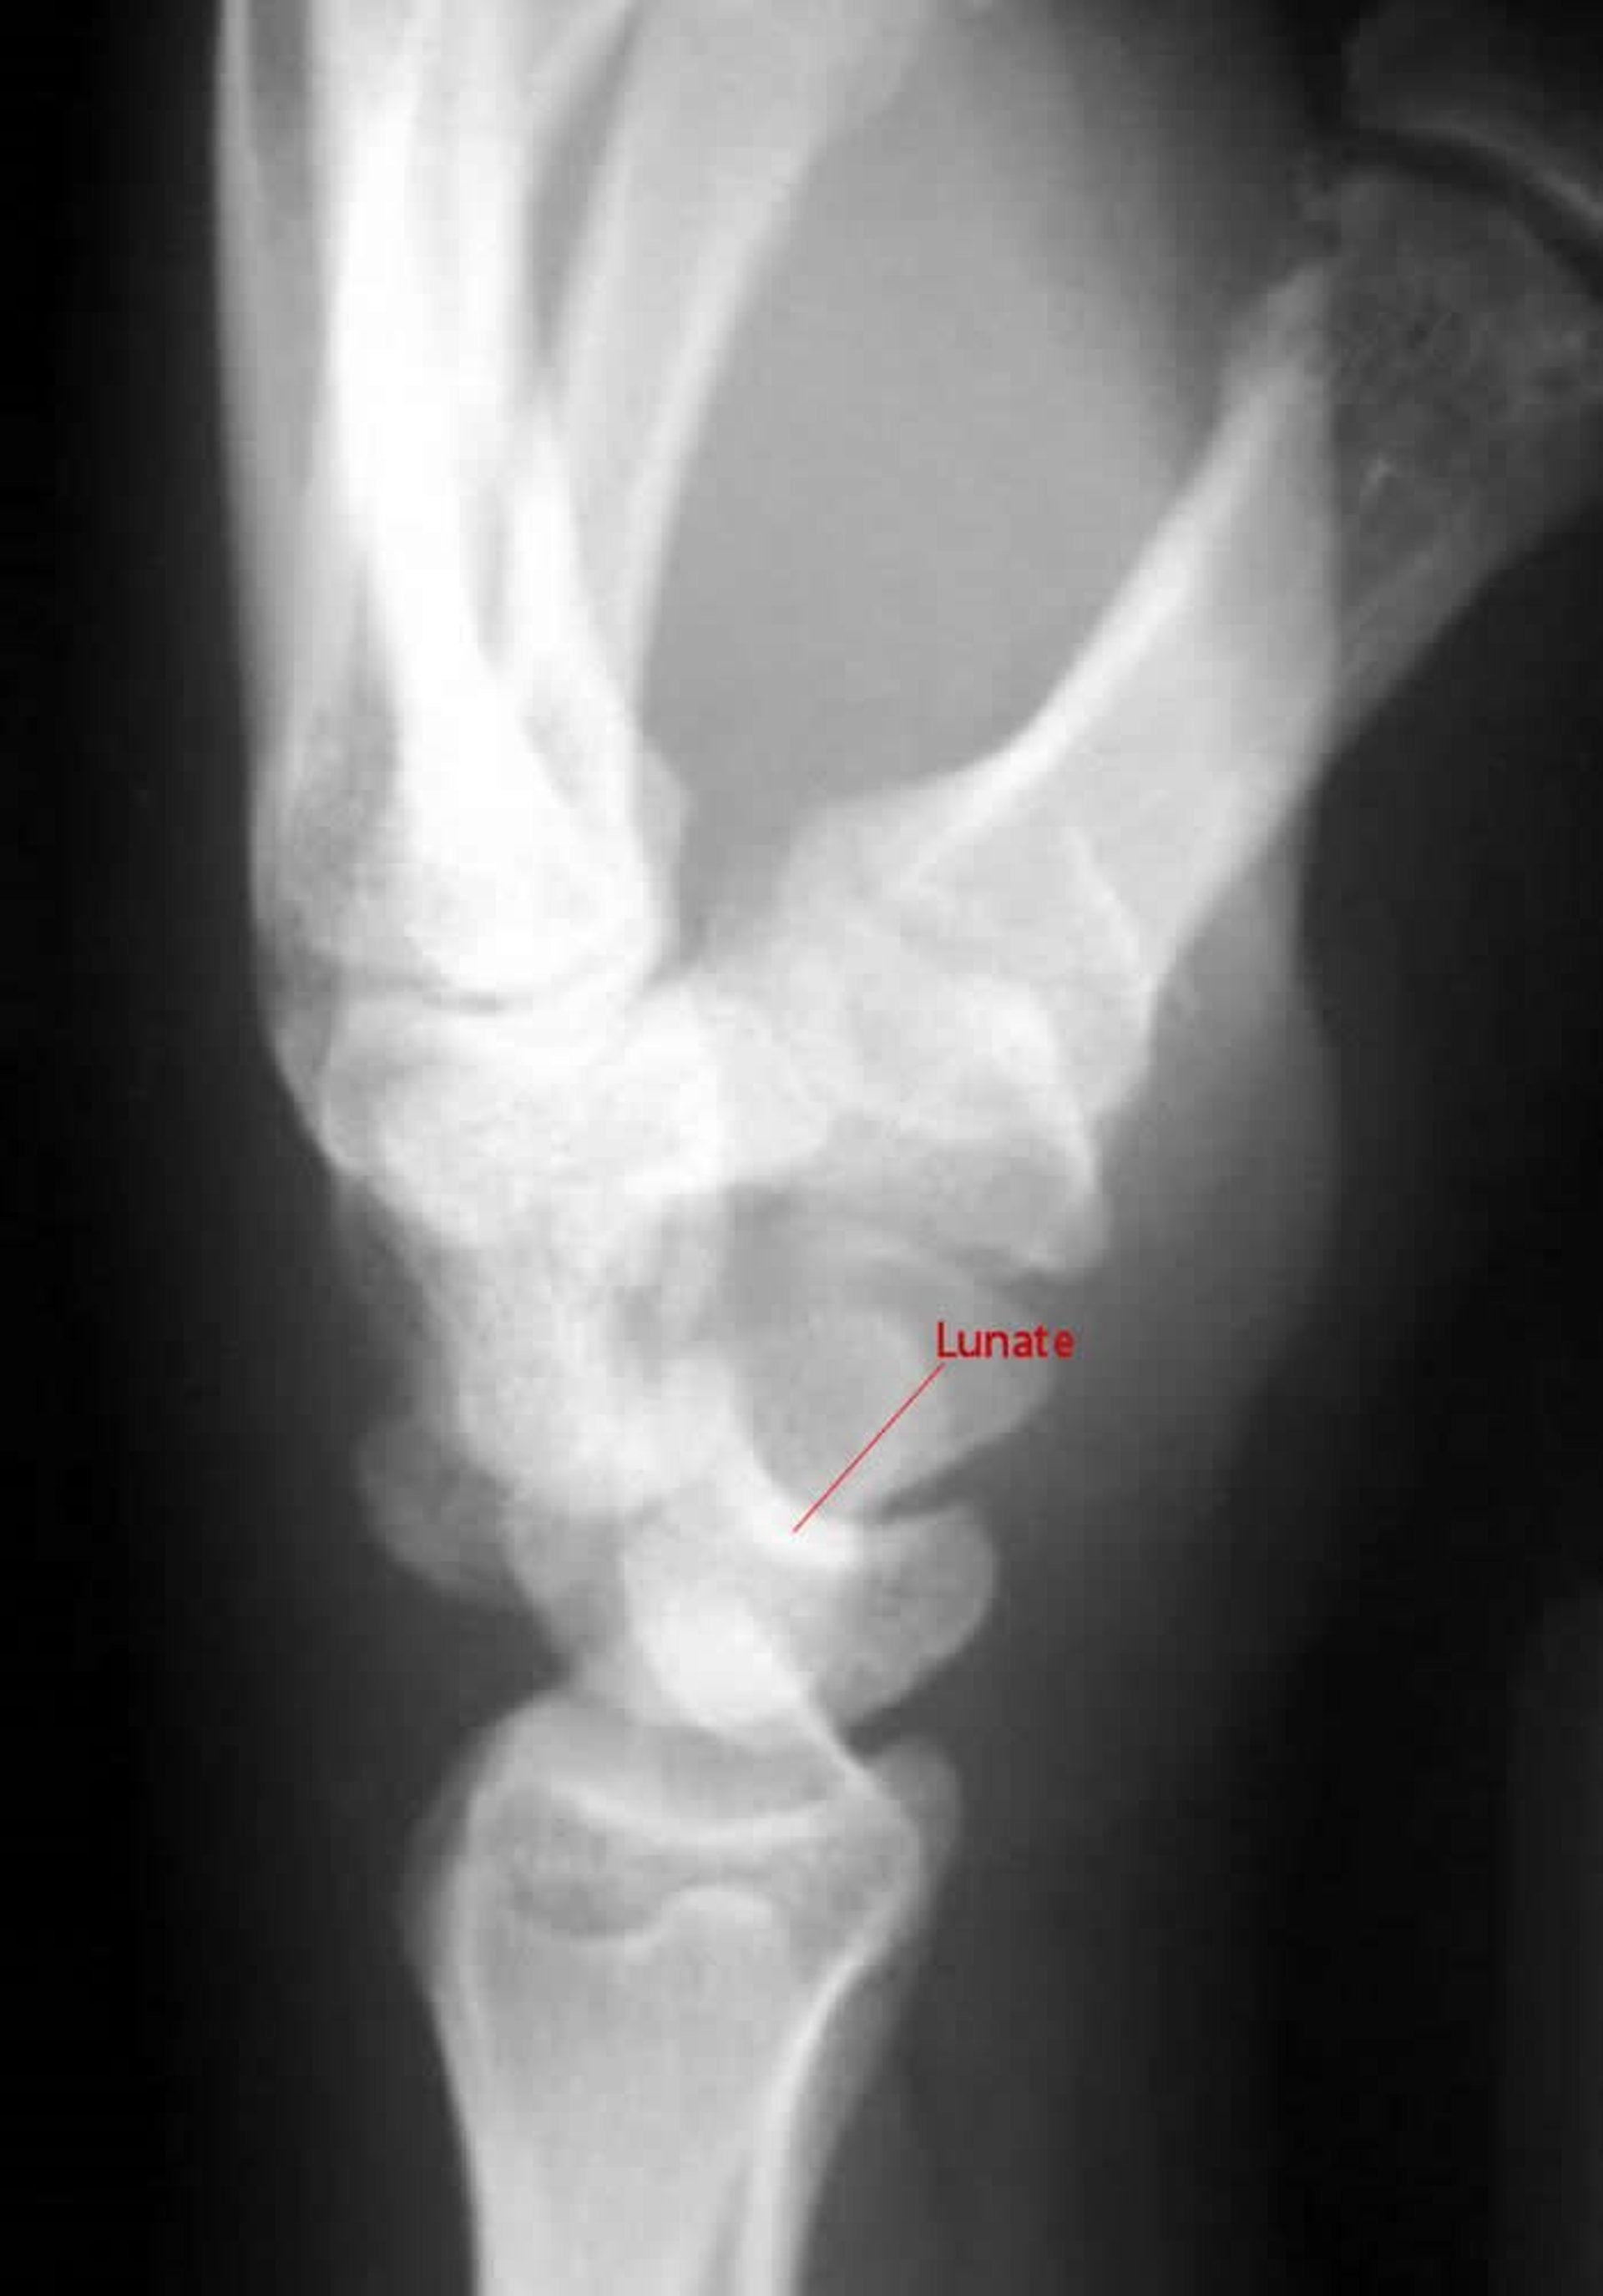

Luxación perisemilunar

En una vista lateral de una luxación perisemilunar, el ganchoso no articula con el semilunar.

Image courtesy of Danielle Campagne, MD.